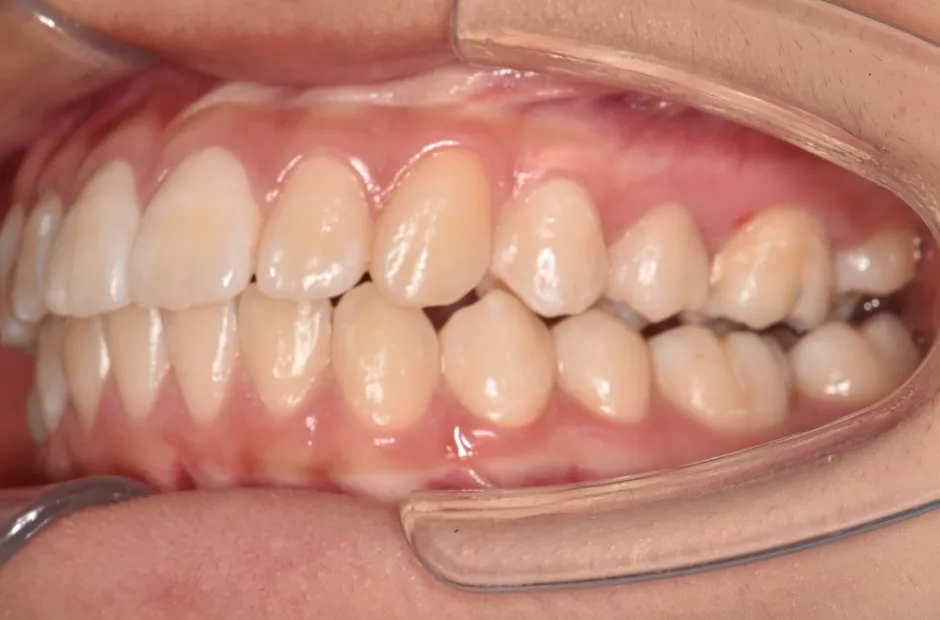

治療症例

ブラケット矯正

前歯部反対咬合

| 診断名・主訴 | 前歯部反対咬合 |

|---|---|

| 年齢・性別 | 14歳・男性 |

| 治療期間・回数 | 1年2か月 |

| 治療に用いた主な装置 | ブラケット矯正 |

| 抜歯部位 | なし |

| 治療費 | 60万円(税抜) |

| リスク・副作用 | 装置による違和感・疼痛・歯肉退縮・歯根吸収・虫歯のリスクなど |

治療前

治療中

治療後